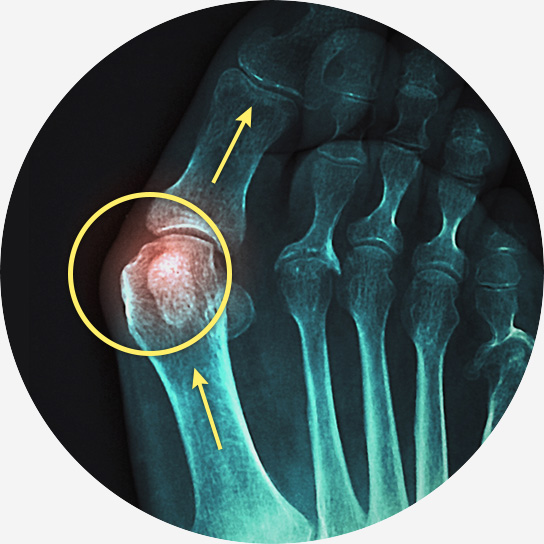

무지 외반증은 엄지발가락이 두 번째 발가락 쪽으로 휘어지면서 발 안쪽으로 튀어나오는 질환입니다.

엄지발가락 관절 부위가 붓고 염증이 생겨 통증을 유발하며, 심한 경우에는 걷거나 서 있는 것조차 힘들어질 수 있습니다.

엄지발가락 관절 안쪽이 튀어나오고 통증 발생